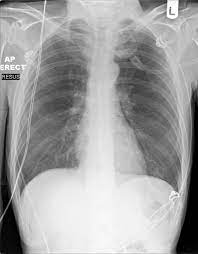

It is often the first imaging test a doctor will order if lung or heart disease is suspected. Each subtype of throat cancer has its own criteria for each stage. The bone at the site of the cancer may look ragged instead of solid. The appearance of throat cancer on the other hand depends on the part of the throat that is affected by cancer and the stage of its development. To evaluate respiratory conditions like asthma, bronchitis, and pneumonia, heart conditions, broken ribs, and to look for fluid and tumors within the chest cavity.

Lung cancer tumors look like white round circles on cxr.

The appearance of throat cancer on the other hand depends on the part of the throat that is affected by cancer and the stage of its development. Lung cancer tumors look like white round circles on cxr. Later stages indicate more advanced cancer, with stage iv being the most advanced. For instance, voice changes may be a sign of laryngeal (voice box) cancer, but they would rarely indicate cancer of the pharynx. Your voice box sits just below your throat and also is susceptible to throat cancer. Let's talk about throat cancer. This mass will look like a white spot on your lungs, while the lung itself will appear black. Sometimes doctors can see a tumor around the defect in the bone that might extend into nearby tissues (such as muscle. If they notice signs of a problem, they'll look carefully inside your mouth and throat, sometimes with a special lighted tool, and may feel your jaw and neck for lumps or patches. Lung cancer and throat cancer sometimes occur at the same time. The most sensitive way to detect throat cancer is to have an. The leukoplakia is apparent under imaging test and cannot be rubbed off. The most common symptom of thyroid cancer is a hard lump on the neck—but most patients experience no symptoms at all.